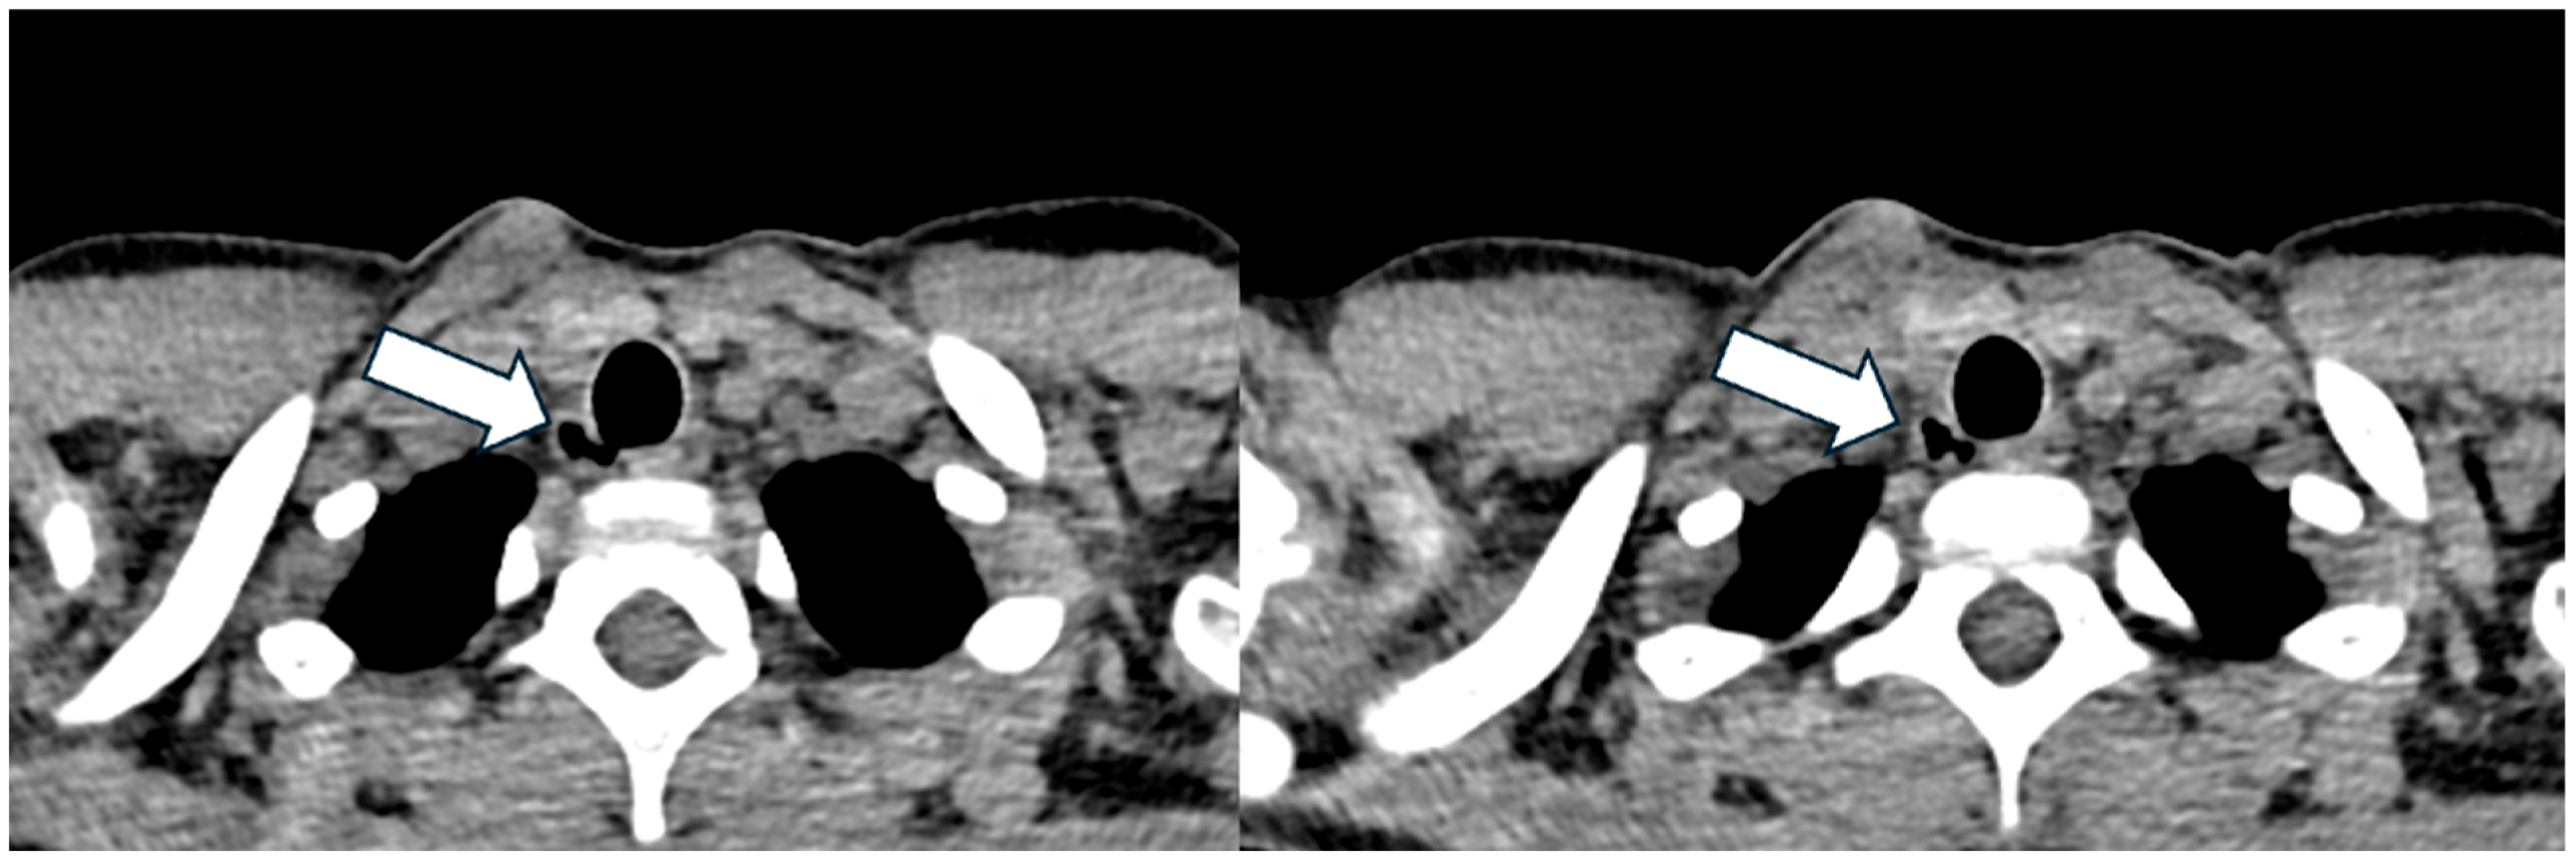

3.3. Patient 3

| 10, F | F508del/ F508del | SA, first PA detection | 117 | 16 | 1, 9, right posterolateral at T1 level | No | Visible radiologically, not endoscopically | Not yet performed |